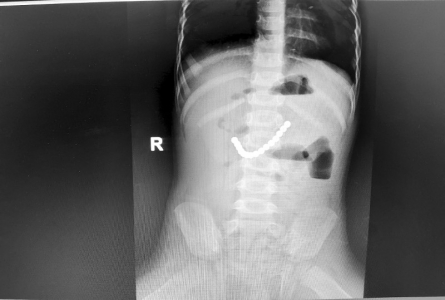

1.患儿:李某某,性别:男,年龄:2岁;简要病史:2岁男孩,因间断腹痛5天,发现消化道异物1天入院。5天前患儿无明显诱因出现腹痛,家长未予特殊重视,1天前患儿出现呕吐伴便秘,就诊于当地医院,行腹部X线片提示消化道异物(磁力球?),遂急诊就诊于我院,诊断“消化道异物(磁力球?)”收住我科。发病后患儿精神食欲差,予以开塞露后排大便1次,小便正常。既往身体健康,无家族遗传病史,心肺腹查体无异常。初步诊断:消化道异物(磁力球?)接下来,患儿需要做什么检查呢?是继续观察自行排出?还是内镜下取出?又或是剖腹探查取出呢?完善腹部X片 (两次间隔时间6小时)显示:磁力球位置未见明显变化(如下图),拟行手术治疗,手术方式为:剖腹探查术。手术探查示 (如下图):胃大弯处可见有2处直径约0.5cm穿孔 (穿孔内取出磁力球5颗),距屈氏韧带约40cm肠管近系膜侧可见2处直径约0.5cm穿孔 (穿孔内取出磁力球10颗),抗菌薇乔全层间断缝合一层胃大弯及小肠肠管穿孔,间断浆肌层加固一层;查无漏气漏液现象,吻合口直径通过顺畅。术毕。术后治疗:予以抗感染、肠外营养、过渡饮食对症治疗,患儿恢复顺利,康复出院。2.患儿:贾某某,性别:男,年龄:1岁10个月;简要病史:1岁10个月男孩,因精神反应欠佳伴烦躁哭闹4天入院。患儿于入院近4天精神反应欠佳,烦躁、哭闹,手捂腹部,呕吐2次,就诊于卫生所予以腹部外敷药物治疗,效果欠佳,后就诊于妇幼保健院,行腹部X片检查,提示消化道异物,自发病以来精神可,食欲欠佳,大便1次,小便量少。既往身体健康,无家族遗传病史,心肺腹查体无异常。初步诊断:消化道异物(磁力球?)完善腹部X片(两次间隔时间6小时)显示:磁力球位置未见明显变化(如下图),拟行手术治疗,手术方式为:剖腹探查术。手术探查示(如下图):距屈氏韧带约30cm小肠有2处直径约0.5cm穿孔(穿孔内取出磁力球1颗、螺丝1颗),距肛门口20cm处乙状结肠近系膜侧可见2处直径约0.5cm穿孔 (穿孔内取出磁力球9颗),据回盲部40cm处小肠系膜可见2处直径约0.5cm穿孔。术后治疗:予以抗感染、肠外营养、过渡饮食对症治疗,患儿恢复顺利,康复出院。